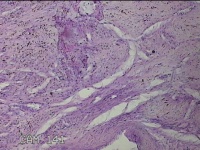

子宫体肌瘤结节

子宫肌瘤 疤痕子宫

发现子宫肌瘤数月余。

灰白色圆柱形条索状组织10x7.5x1.8㎝一堆,切面均为灰白色结节状或编织状,质中。